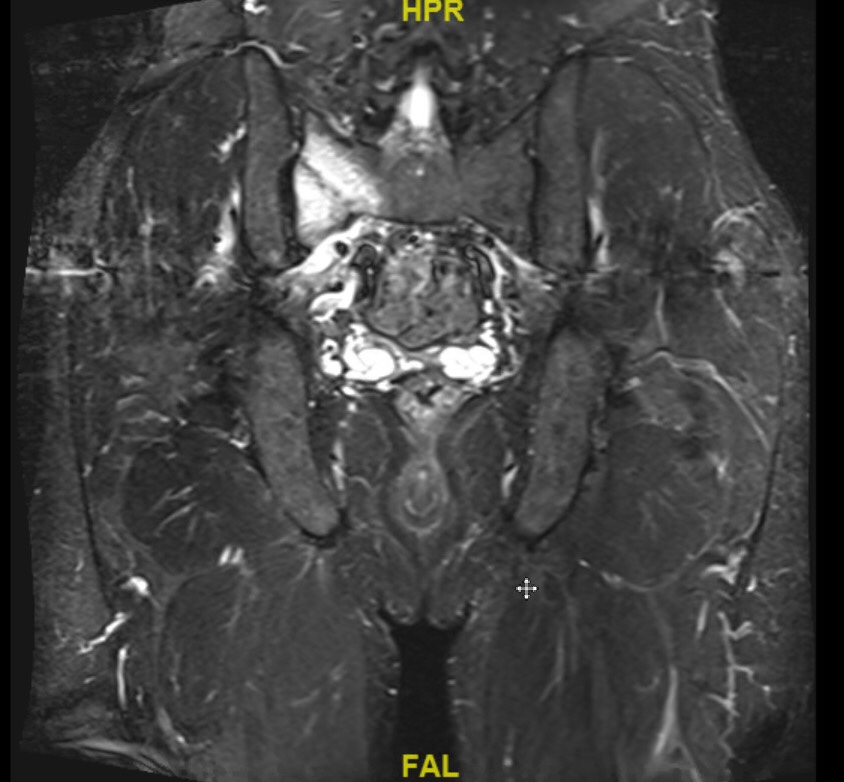

Eventually I saw a new physician and an MRI showed a right sacral stress fracture. My guess is that this was the result of too rapid a build up I pushed for after my summer “vacation” from running.